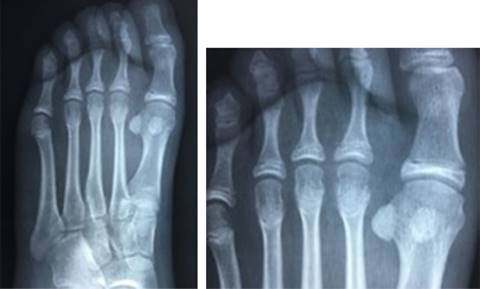

Con previo consentimiento de los padres y la paciente, bajo anestesia local con lidocaína al 2% (3 cm3), se realiza reducción cerrada de la fractura epifisaria mediante tracción del segundo dedo y digitopresión en dirección plantar de la cabeza del metatarsiano. Se toman radiografías de control posterior al procedimiento; se encuentra reducción anatómica de la fractura (Figura 2). Se colocó zapato postquirúrgico por cuatro semanas y se reincorporó a actividades de la vida diaria dos meses posteriores a la fractura. Se realizó seguimiento clínico y radiológico de forma esporádica sin complicaciones en su evolución, se anexa radiografía a 36 meses de evolución (Figura 3).

Figura 2: Radiografías anteroposterior y oblicua del pie derecho, posterior a reducción cerrada. Se muestra adecuada reducción de fractura epifisiaria del segundo metatarsiano.